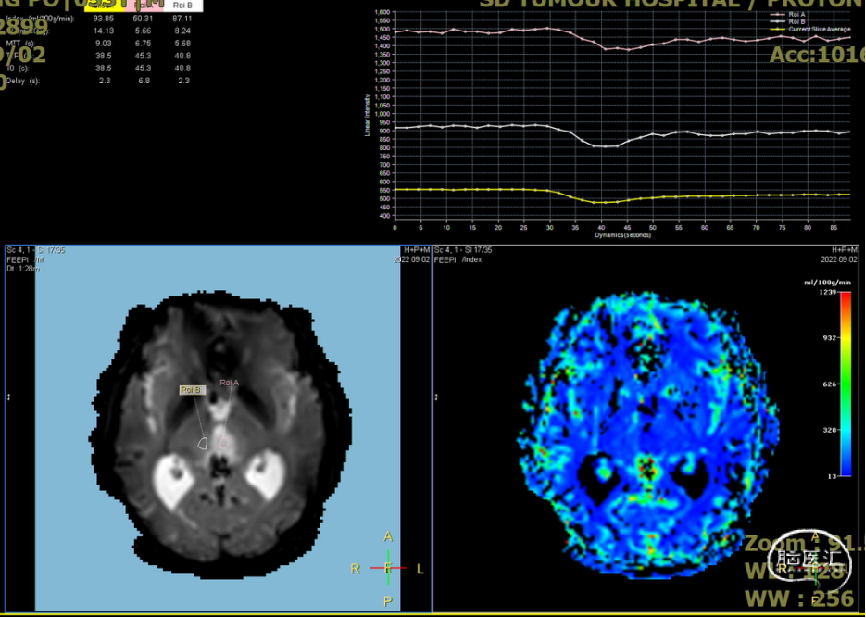

入院检查

患者5年前无明显诱因出现阵发性头晕,无明显头痛、恶心呕吐等不适,开始未予重视,2022-7-19出现头晕加重,伴视力下降,遂于2022-7-24在当地医院行颅脑MRI提示:松果体区肿瘤伴梗阻性脑积水。